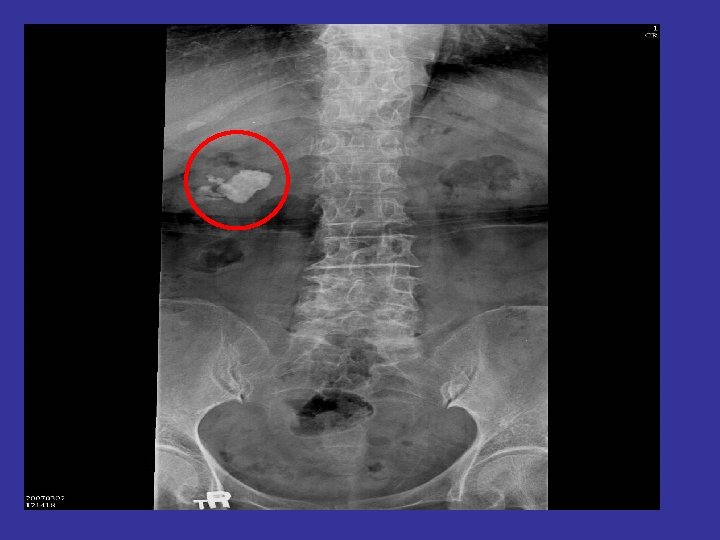

The Patient • Past history : Hypertension under regular control Senile dementia (mild) • Preoperative diagnosis : Right renal stone (3. 2 cm) • Operation planned : Right PCNL (percutaneous nephrolithotomy)

Preop